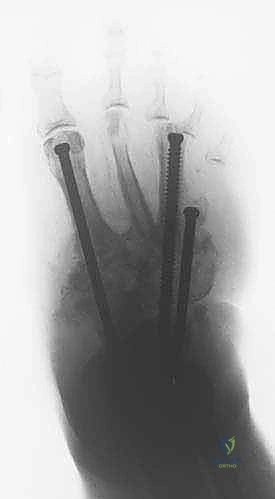

- التدخل المحدود: بدلاً من شق القدم بالكامل، يتم عمل ثقوب صغيرة جداً (بضعة مليمترات) في الجلد.

- إدخال الأسلاك: يتم تمرير أسلاك معدنية رفيعة جداً وقوية (K-wires) ومسامير نصفية (Half-pins) عبر العظام في الساق والقدم بأماكن استراتيجية محددة مسبقاً بدقة لتجنب الأعصاب والأوعية الدموية، وذلك تحت توجيه الأشعة السينية المباشرة (C-arm) في غرفة العمليات.

- تجميع الإطار: يتم توصيل هذه الأسلاك بحلقات خارجية معدنية أو كربونية تحيط بالساق والقدم (إطار إليزاروف). يتم تثبيت هذه الحلقات معاً بواسطة دعامات قابلة للتعديل.

3. مرحلة التصحيح التدريجي (Gradual Correction Phase)

تبدأ هذه المرحلة بعد أيام قليلة من الجراحة. يقوم المريض (أو مرافقه) بتدوير صواميل معينة على دعامات الجهاز الخارجي بمقدار محدد جداً (عادة 1 مليمتر في اليوم).

* هذا الشد البطيء يسحب العظام المنهارة لتعود إلى مكانها الطبيعي.

* يصحح التشوه دون التسبب في صدمة للأنسجة.

* يسمح بتكون أنسجة جديدة (Distraction Histiogenesis).

تستمر هذه المرحلة لعدة أسابيع حتى يتم الوصول إلى المحاذاة التشريحية المثالية واستعادة قوس القدم.